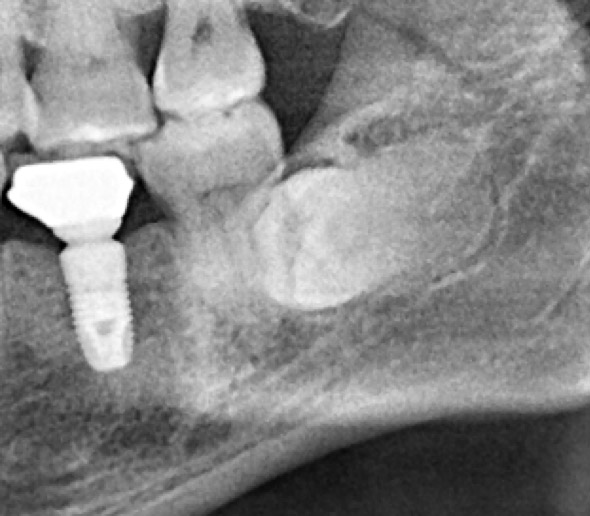

☆本院特別巨資增設 ”千萬級3D AI透視電腦斷層”,並配合“成骨膠原蛋白”施作 (上述兩項目前健保無給付),讓您遠離神經傷害、口鼻竇(炎)相通...等併發症,除健保之外,難免會有避免併發症風險的自費項目,網路上經常會有看到智齒拔完後唇麻、舌麻、口鼻竇相通等併發症,在本院嚴格自我要求下,此類併發症在本院幾乎趨近於零。

外面拔時易斷裂於骨頭內而難以取出